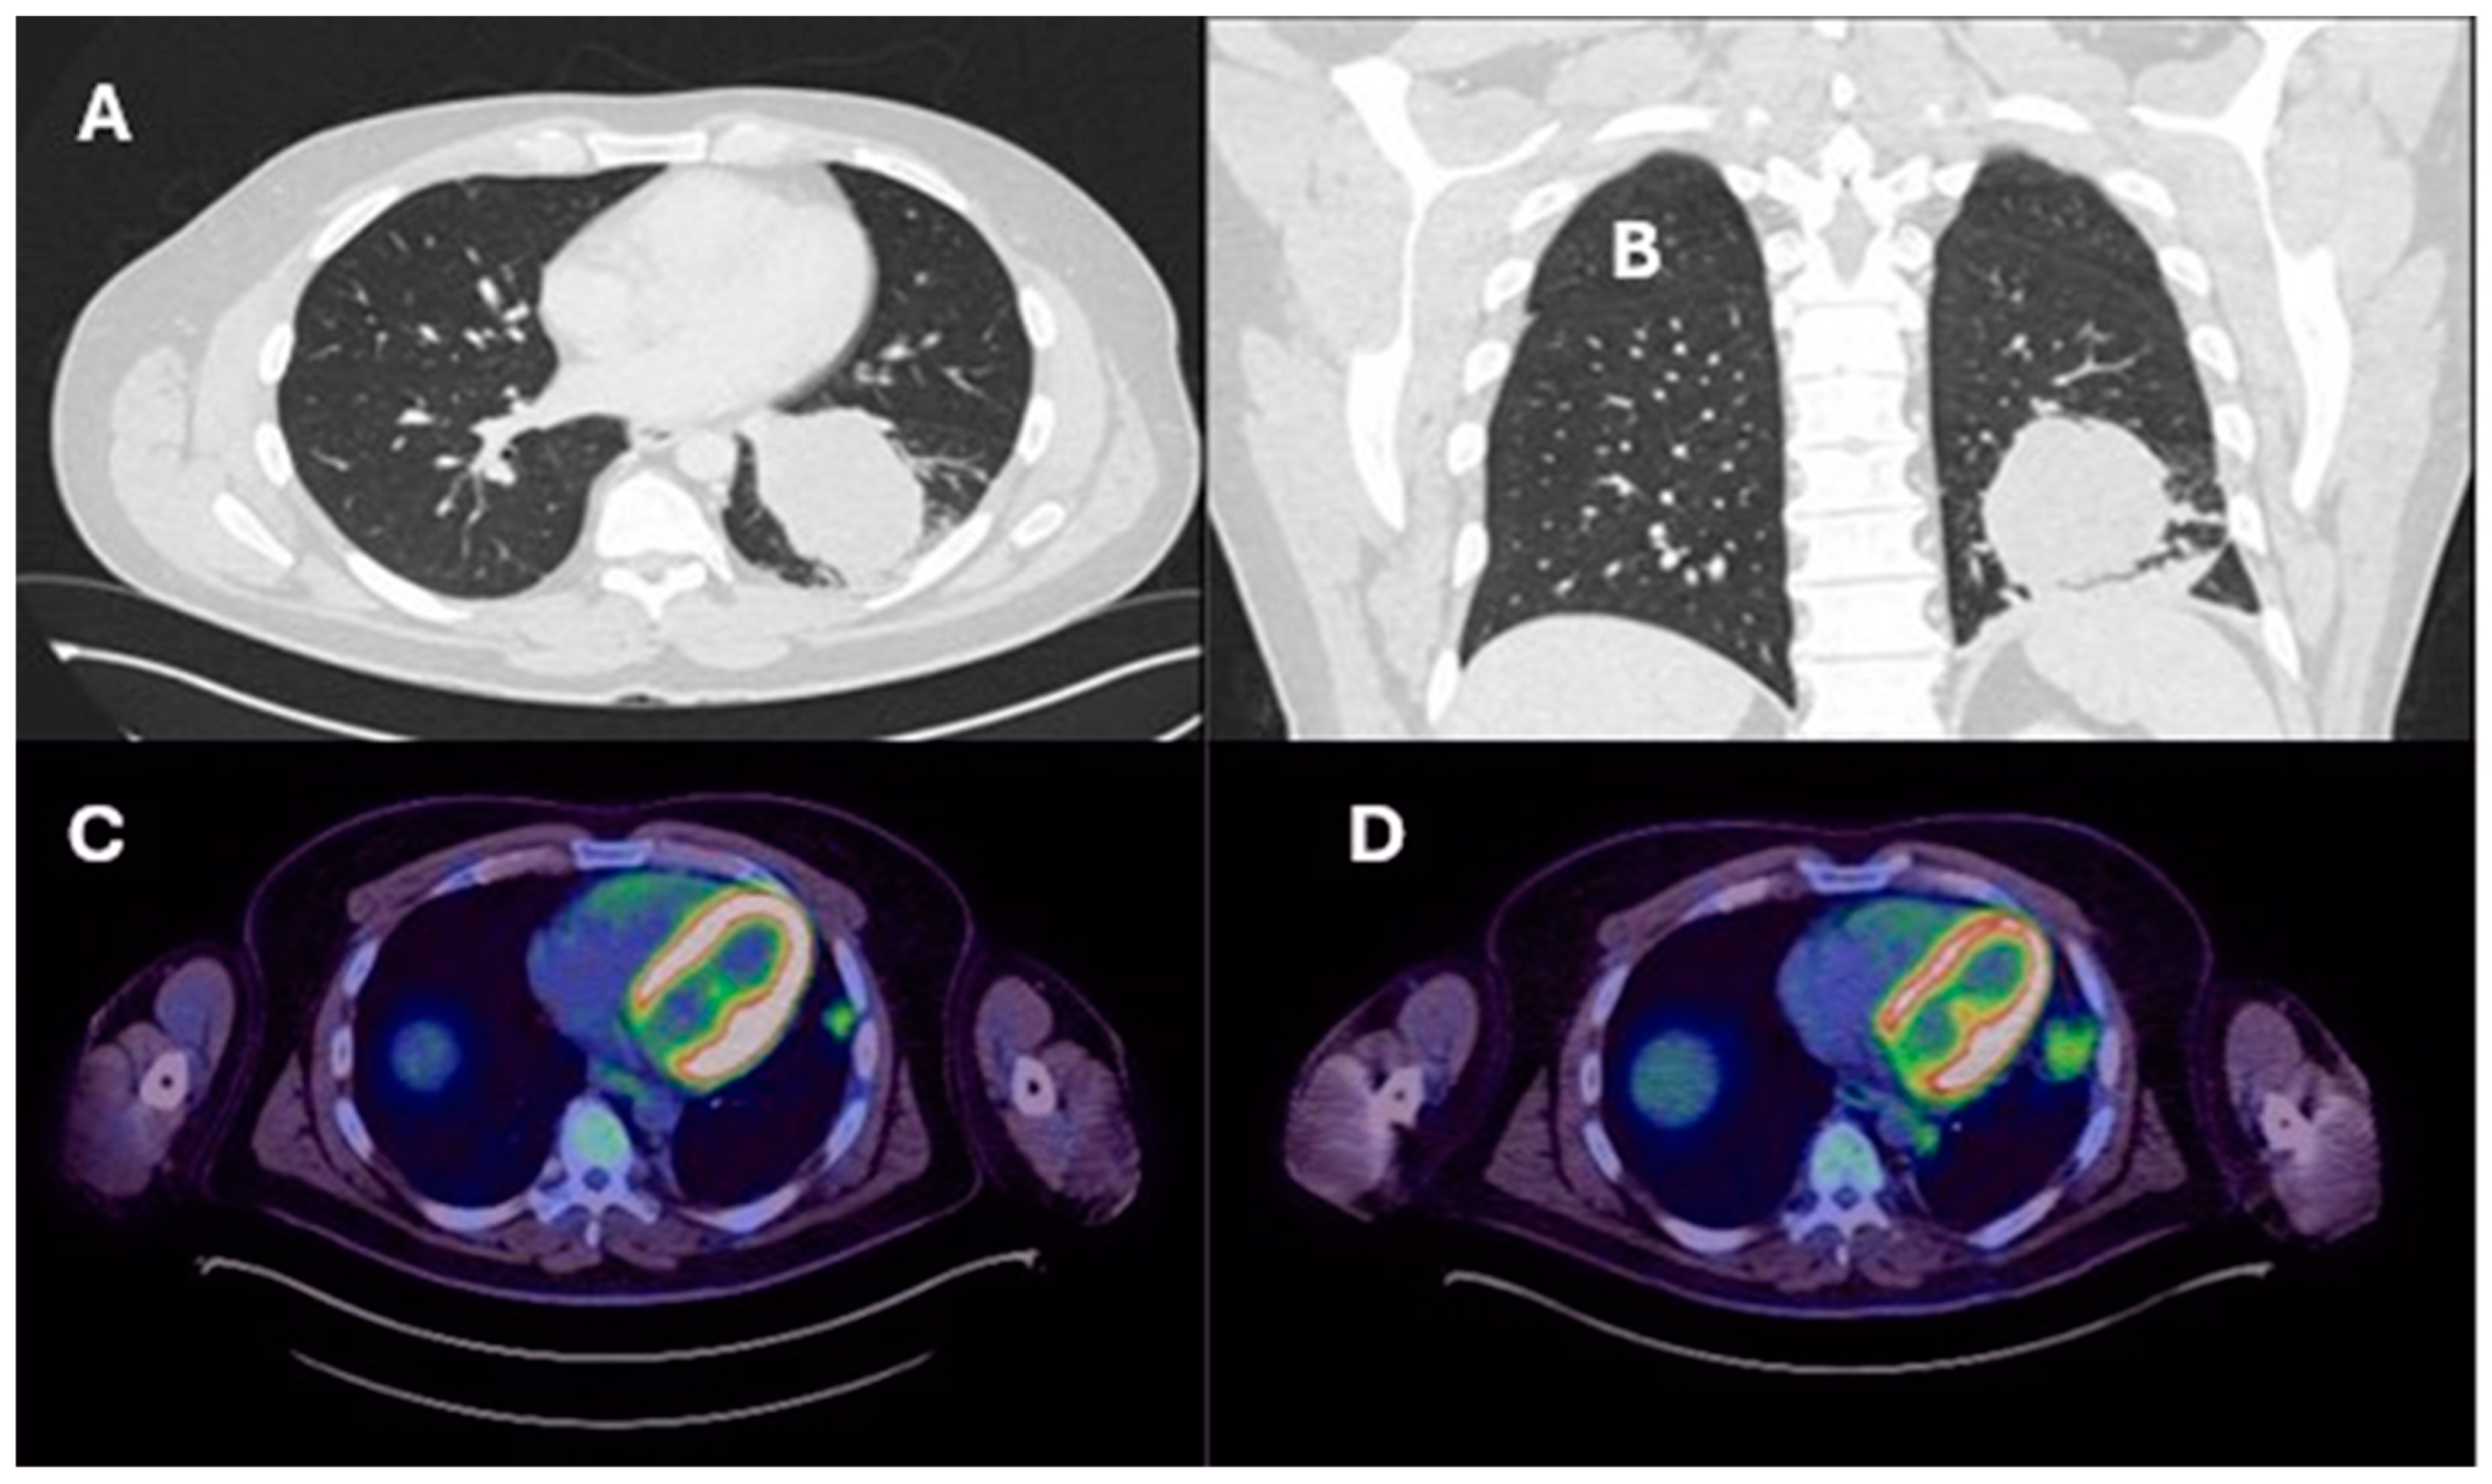

| Lung resection November 2022—Left lower lobectomy + lymph node dissection: pT3pN0 R0 resection. SMARCB1-deficient, PDL1-negative, TTF-1 negative, CD56-positive, cytokeratin positive. Pre-operative CT axial and coronal slices are shown in Figure 2A and Figure 2B, respectively. | Lung resection January 2022—right upper lobectomy + lymph node dissection: pT1cpN0 R0 resection. SMARCB1-deficient, PDL1 negative, TTF-1 negative, CD56-positive, cytokeratin-positive. Pre-operative axial PET slice shown in Figure 3A. |

| Recurrence December 2022—started 4 cycles of Gemcitabine/Cisplatin. Post-operative recurrence demonstrated in PET slices (Figure 2C,D) | Recurrence June 2022—progressive disease noted on CTPA (performed for SOB, pyrexia) at the right hilum, with soft tissue thickening at resection margins. Commenced on Pembrolizumab/Paclitaxel/Cisplatin with systemic intent. Recurrence shown in station 4R (Figure 3B), at the right hilum (Figure 3C) and in the right posterior bony skeleton in ribs 6–9 (Figure 3D). |